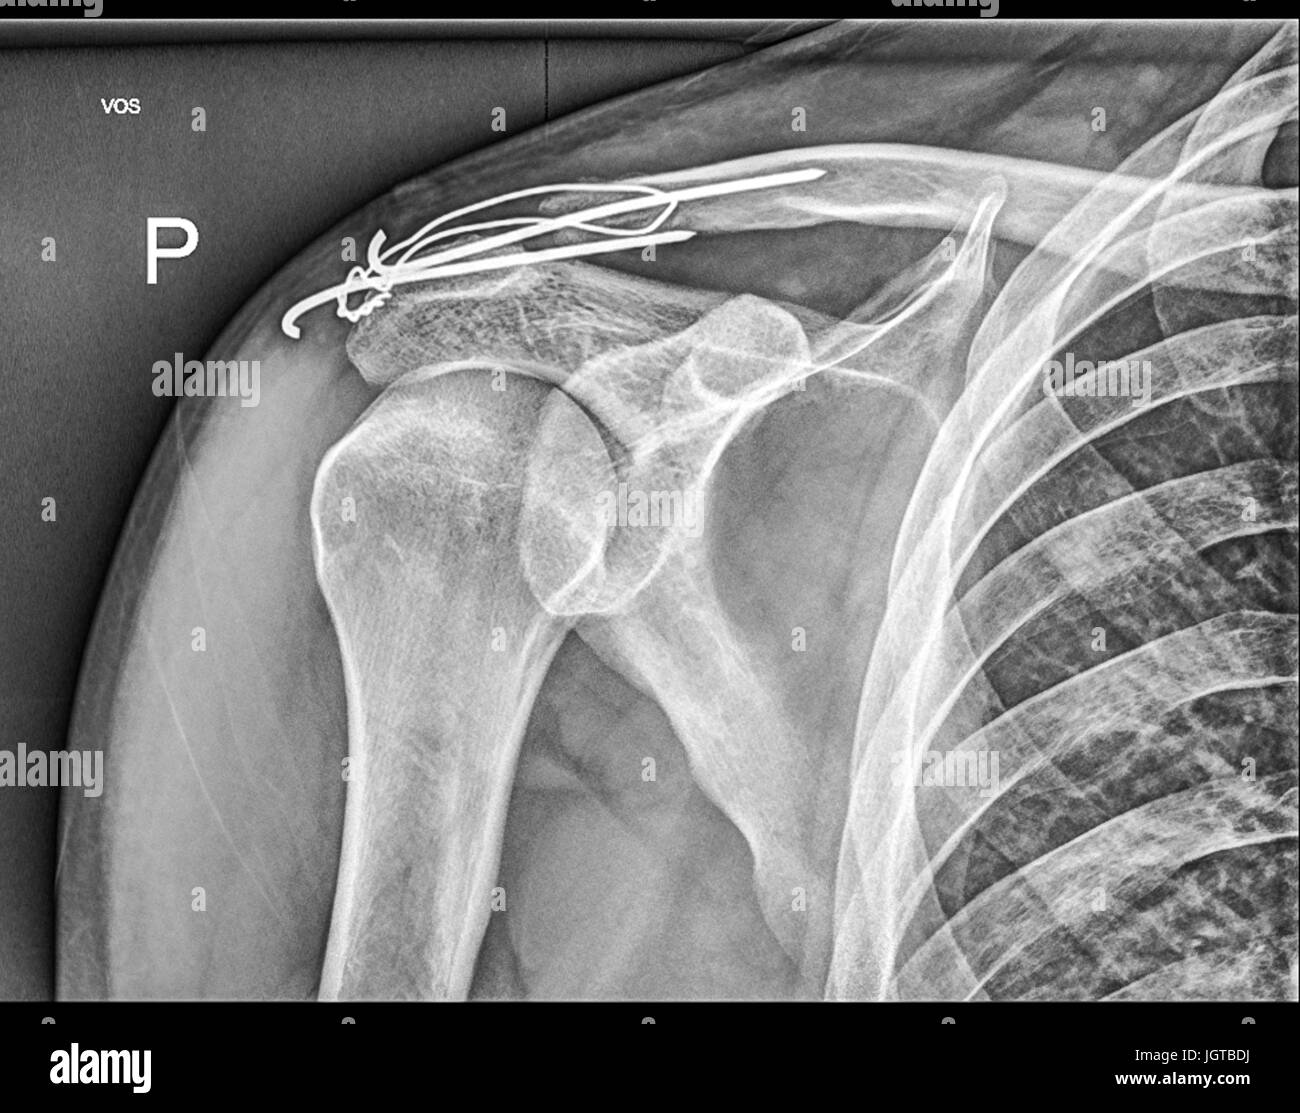

From www.alamy.com

Film xray clavicle AP show fracture clavicle bone Stock Photo Alamy Clavicle Nailing Procedure  The velox tm procedure with sonoma crx® is faster, streamlined, and designed for reproducible, minimally invasive clavicle fracture repair. It is also a procedure best reserved. Intramedullary nailing of the clavicle is reserved for young and highly active patients who are expected to resume full active function soon after surgery. Nailing approach to the clavicle and many more surgical approaches. Clavicle Nailing Procedure.